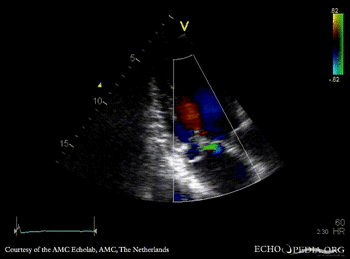

| A3CH with Color Doppler, moderate late systolic mitral regurgitation